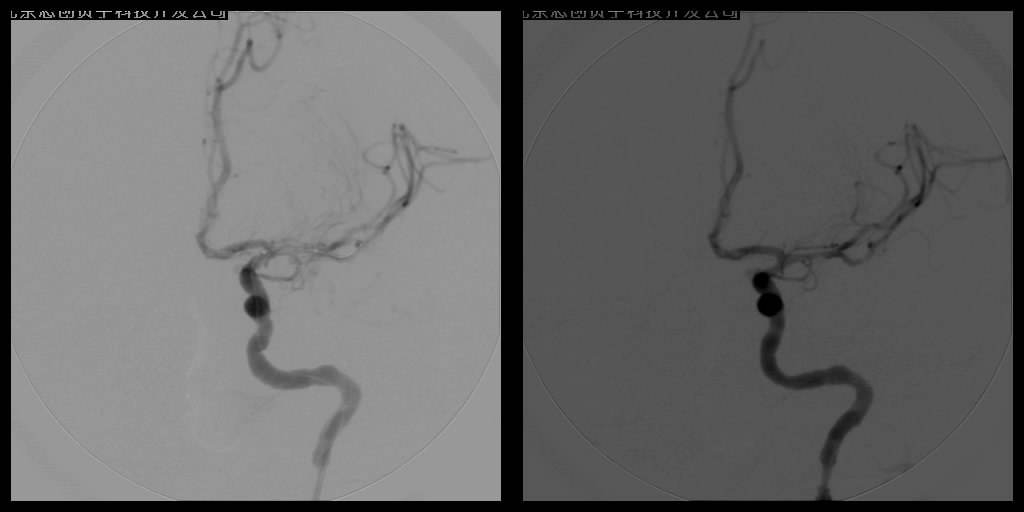

2.动脉血管成形术

针对颈动脉和椎基底动脉狭窄等缺血性脑血管病的防治,血管球囊扩张成形术和血管内支架植入成形术已经成为治疗颈动脉狭窄及椎基底动脉狭窄十分重要的手段,所用支架可分为球囊扩张式支架和自膨式支架。

支架植入